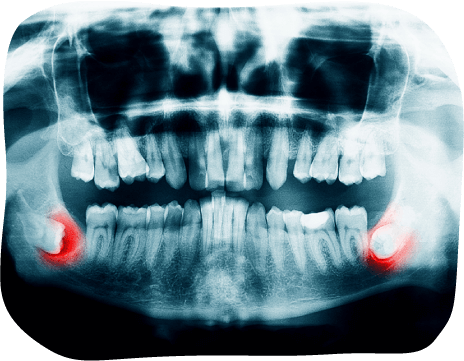

歯のレントゲン写真

親知らず

親知らずは一番奥にあるため、歯ブラシが届きにくく、むし歯・歯ぐきの腫れ・隣の歯のむし歯などトラブルが起こりやすい歯です。

痛みがあるときは、すでに手前の健康な歯まで影響していることも多く、放置すると抜歯+追加治療が必要になるケースもあります。

抜歯をおすすめするケース

• 手前の歯と同じように生えているが、清掃が不十分な場合

• 一部だけ歯が見えている場合

• 横向き・斜めに生えている場合

• 骨の中に埋まっていて、レントゲンで問題がある場合

• 歯並びへ悪影響が出る恐れがある場合

抜歯に適した時期

20〜30代の若いうちが最適 です。骨が柔らかく抜きやすいため、処置の負担が少なく済みます。

また、痛みや腫れがあると麻酔が効きにくく、症状が落ち着くまで抜歯ができない場合があります。